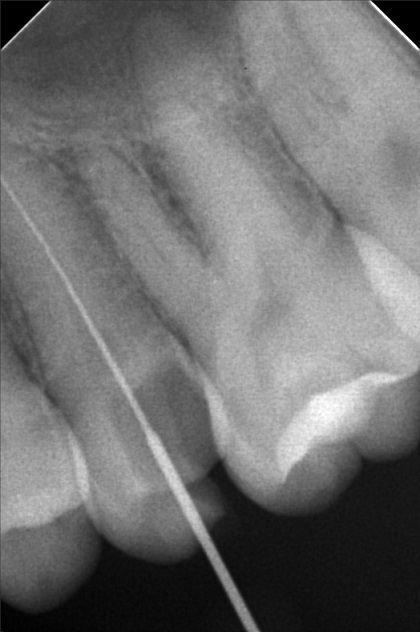

Edit Record Check our patient data records. Add patient information Patient Info Profile picture Last Name First Name Middle Name Birthdate Age Street Barangay City Country Zip Code Contact number Email Procedure 10/01/22 - OP(L); RESTO #26 ; #48; ACCESS #25 Scouting file #10 20mm; Closed with formocresol; Prescribed Tramadol +Paracetamol 325mg 10/08/22 - FILE 35 -19mm, CLOSED W/ CAMPHENOL; RESTO #22(LINGUAL), #47 (O & BUCCAL PIT) 10/15/22 - FILE 35 - 19mm, CLOSED W/ FORMECRESOL, RESTO #18(OB), #27, #28 10/22/22 - OBTURATE, FINAL RESTO#25, RESTO #16 (OL), #38 (O) File jamjam.jpg File 2 jamjam_02.jpg File 3 jamjam_03.jpg File 4 jamjam_04.jpg File 5 jamjam_05.jpg File 6 File 7 File 8 File 9 File 10 File 11 File 12 File 13 File 14 File 15 File 16 File 17 File 18 File 19 File 20 Retain Record Retain Record Yes No Save Your Changes